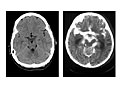

- Imaging tests.

An MRI or CT scan may show bleeding, swelling, or other changes in the brain caused by encephalitis.